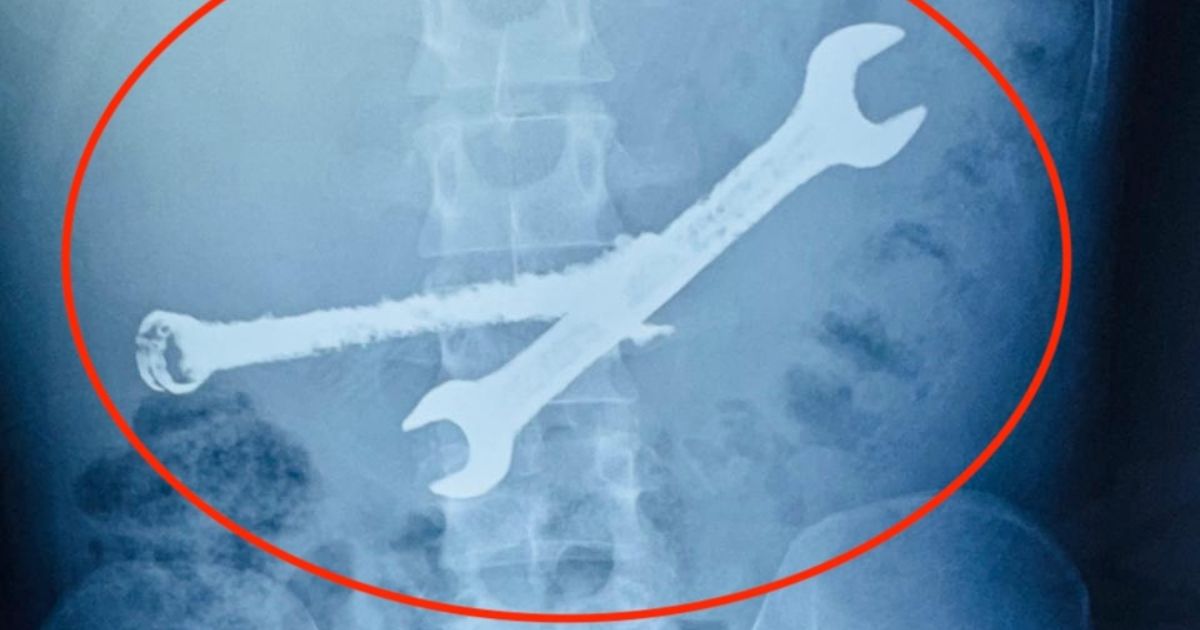

NE ZNAJU KAKO JE ŽIV! Mladić (26) se žalio na bolove u stomaku: Kad je stigao rendgenski snimak, nastao muk

Bizarna priča stiže iz indijske države Radžastan.